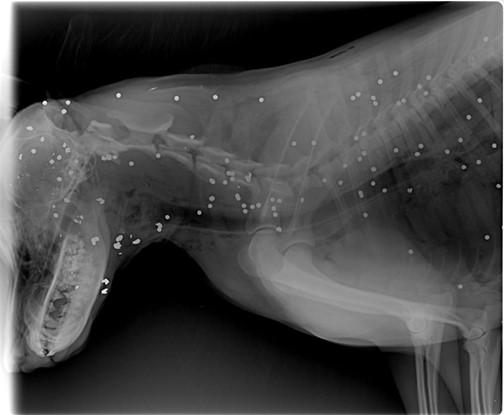

Více jak 100 broků v Theovi, který byl zabit myslivcem!

[iii]

V souladu se statistikami Českého statistického úřadu jsou ročně myslivci zastřeleny stovky psů a vyšší tisíce koček. Jedná se však pouze o případy myslivci ohlášené a reálně tak může jít o značně vyšší než uvedená čísla. K usmrcení domácích mazlíčků přitom dochází zcela bezdůvodně a pouze za účelem uspokojení sadistických potřeb některých myslivců.